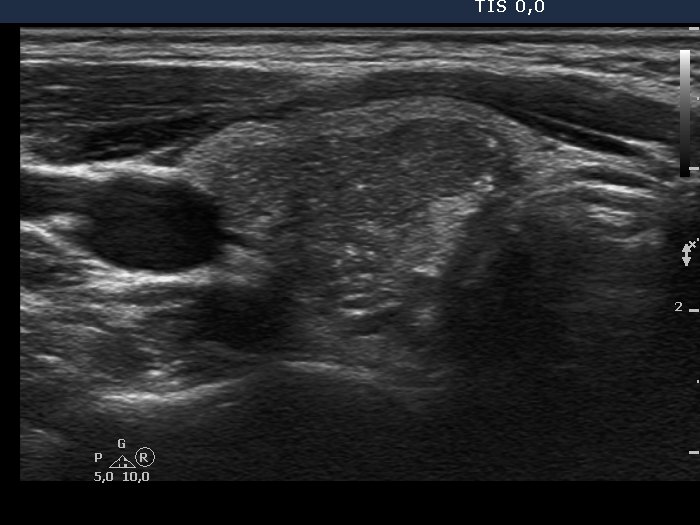

Oxyphilic adenoma (histological diagnosis) - case 1735 |

Papillary carcinoma (histological diagnosis) |

Both lesions have multiple cystic areas. The malignant case clearly belongs to spongiform cyst category because the cystic area exceeds 50% of the nodule. The risk of malignancy is very low in such lesions if there are no signs suggesting an increased risk. The solid part was hypoechogenic in these cases therefore aspiration cytology was mandatory. Note that both cases presented signs of posterior acoustic enhancement, i.e. hyperechogenic figures in the back wall of the microcystic areas. There was only one but an important difference between the cases. The benign nodule was located within the thyroid, while the malignant was found in a lateral aberrant thyroid tissue.